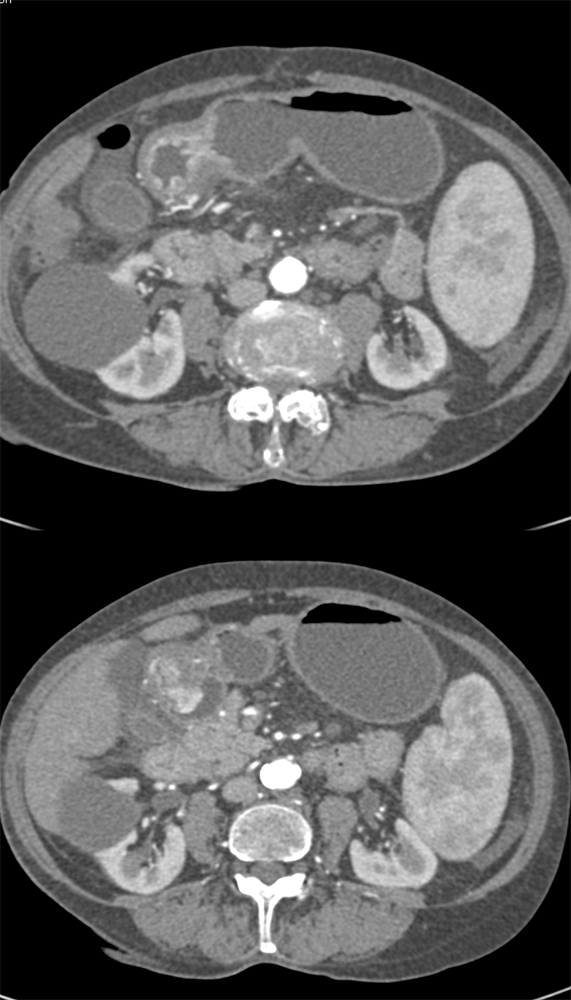

Watermelon stomach (WMS), or gastric antral vascular ectasia (GAVE) ![]() |

“In our patient, the findings of prominent mucosal folds extending from the pylonic channel on upper gastrointestinal series and the thickened antral wall on CT scans correlate well with the known pathologic appearance of gastnic antral vascular ectasia. Histologically, antral thickening results from a combination of foveolar and fibromuscular hyperplasia. Grossly, the antral fold prominence appears to result from bunching of the mucosa in the thickened, hypercontractile antrum.” Gastric antral vascular ectasia ("watermelon stomach"): radiologic findings. Urban BA, Jones B, Fishman EK, Kern SE, Ravich WJ. Radiology. 1991 Feb;178(2):517-8. |

“Gastric antral vascular ectasia primanily affects women (9:1 female-to-male ratio) aged 56-76 years, and is associated with liver cirrhosis (37%) and achlorhydnia (35%). The usual symptoms are iron-deficiency anemia and melena due to chronic gastrointestinal bleeding from the dilated, superficial, and easily traumatized vessels. Antrectomy is curative, but endoscopic treatment with heat probes or lasers has shown promise.” Gastric antral vascular ectasia ("watermelon stomach"): radiologic findings. Urban BA, Jones B, Fishman EK, Kern SE, Ravich WJ. Radiology. 1991 Feb;178(2):517-8. |